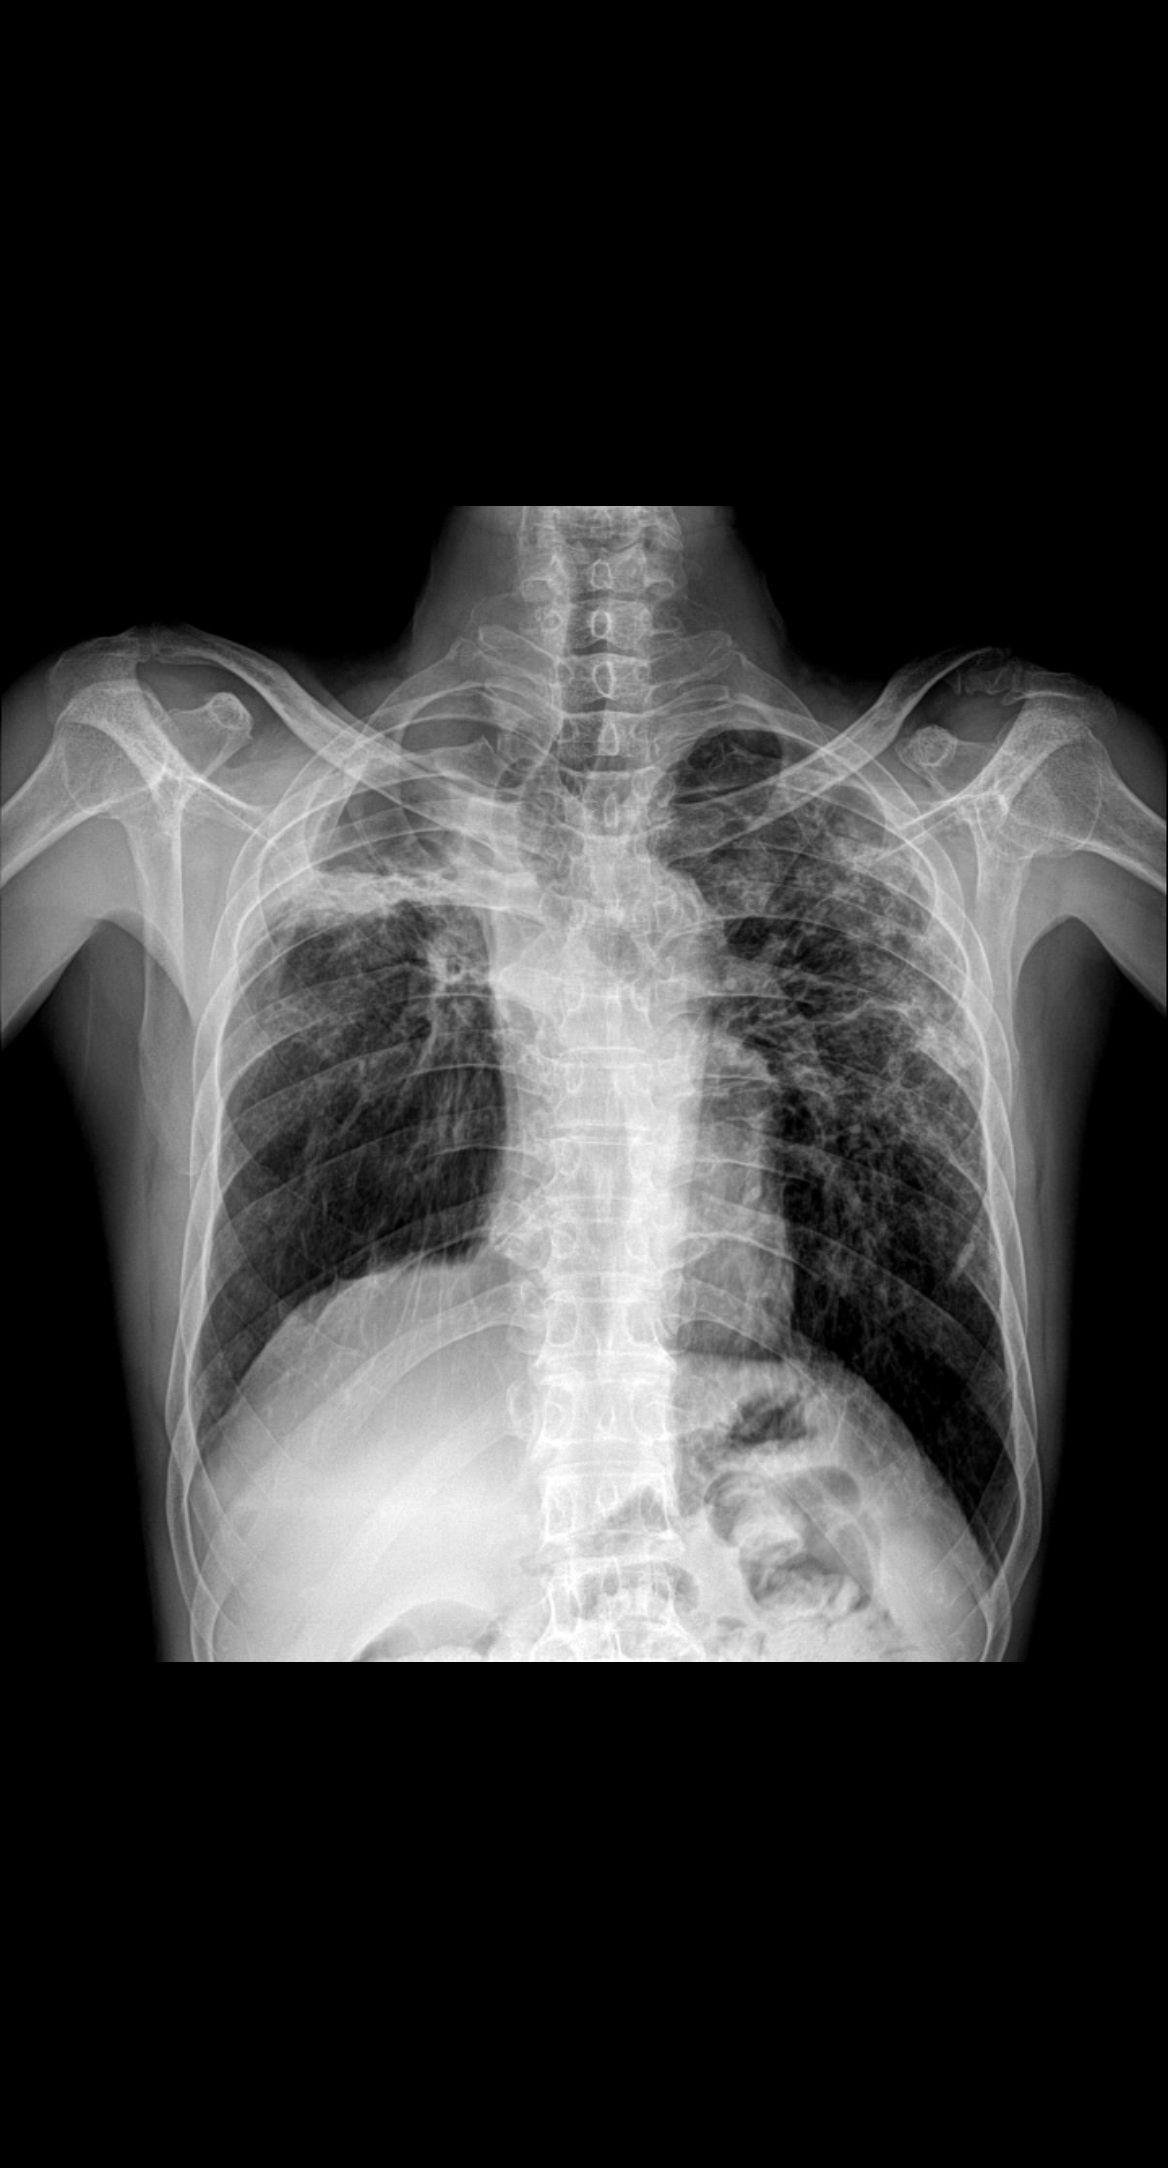

体征:车祸术后两年,颈椎疼痛就诊